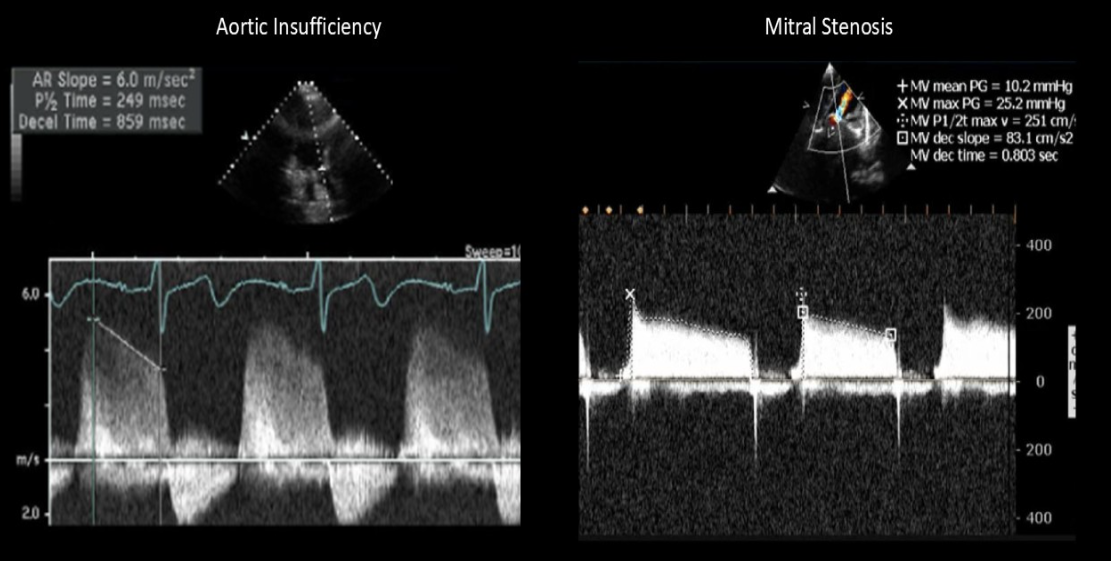

Doppler waveform most suggestive of?

MVP